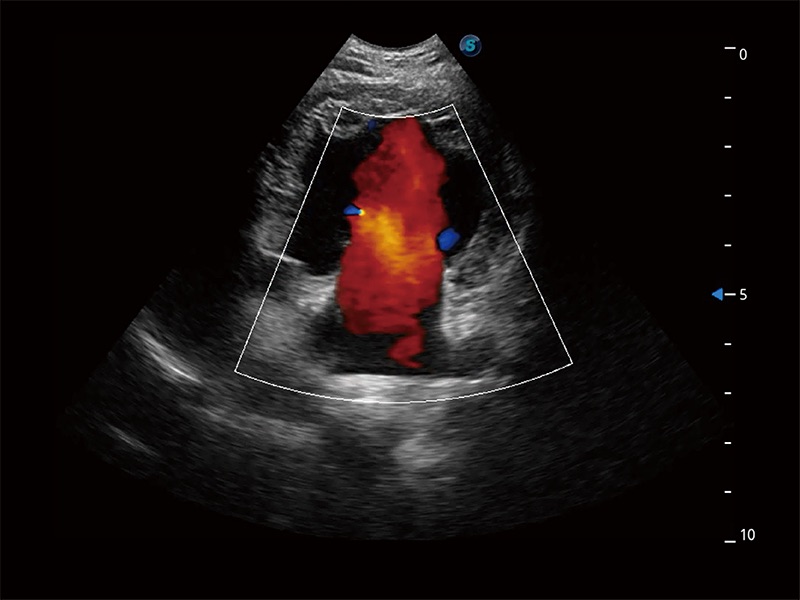

极大提升超低速微细血流的检出能力,同时更精准地滤除软组织和超声信号,为兽用医生提供以往无法通过常规血流获得的疾病诊断信息。

在传统二维血流成像的基础上,呈现血流的立体感,具有动感的生命力之美。即便是微小的血管也能轻松应对,提高了血流的视觉敏感性。